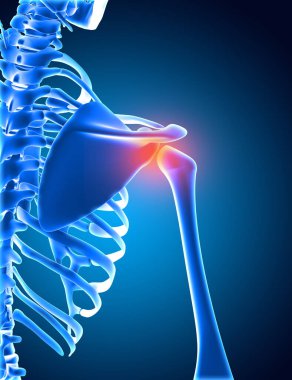

Kalça protezi x-ray 3D görüntüleme. Toplam kalça eklemi değiştirme ameliyatı veya artroplasti, tıbbi ve sağlık, artrit, patoloji, bilim, osteoloji, ortopedi kavramları.

resimlemeyapaymetalİnsanSağlıkİlaçSağlık hizmetleriTıbbiKökKemikgövdeterapiMetalikHastalıkbiyolojiBilimAcıtitanyumkoşulkemiklerEklemgörüntü oluşturmaKalçaİskeletanatomiprotezx ışınıAmeliyatToplamdüzensizlikRomatizmaDeğiştirmeOrtopediPatolojianatomikİmplantArtritleğenLeğen kemiğiKemik iltihabıfemoralUyluk kemiğiromatoidüstteRomatolojiasetabülerartroplastifemur başıBenzer İçerikler